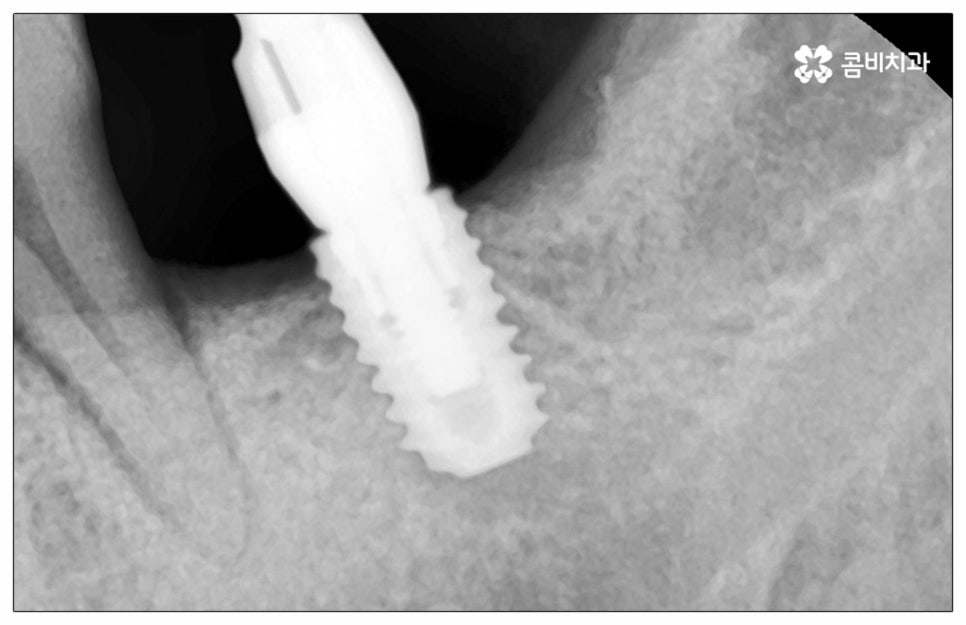

이때 추가 수술은 비급여 항목으로 건강보험임플란트 대상에서 제외되니 이에 대해서도 꼼꼼하게 살펴보시고 정밀 검진 후 담당 의료진과 자신의 상황에 대해서 충분하게 상담해 보시길 권유드리고 있습니다. 추가 수술의 대표적인 예로는 뼈이식 수술이 있는데요. 이것은 임플란트를 식립할 때 바탕이 되는 잇몸뼈의 높이나 폭, 밀도 등이 부족하다면 먼저 이를 보충해 주고 나서 임플란트를 심어주는 과정을 의미하며 같은 이유로 식립 성공률이나 장기적인 안정성을 높이기 위해 꼭 필요한 사전 처치, 즉 상악동 거상술 및 치주 질환 관련 수술 등을 먼저 해야 한다면 이 역시 추가 수술의 범주로 들어가니 자신의 상황에 대해서 상세하게 알아보실 필요가 있어요.